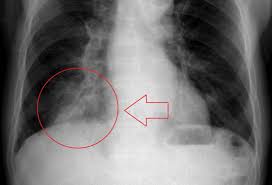

If you feel pain when you inhale, are breathing shallowly, have a cold, or have a history of coughing or bronchitis, it may be lung pain. Sometimes, people with pneumonia may have symptoms similar to lung cancer. How to detect lung cancer: Lung cancer is a common cause of finger clubbing; Symptoms of metastatic lung tumors depend on the location and size. The goals of treatment are to cure the infection and prevent complications. In both cases, you may have. It took about 3 months to fully get over the cough. According to a 2018 study published in the journal of transitional lung cancer research. As for weakness in my arms, that's a tricky one to pin down. The less severe of the two, acute bronchitis is caused by inflammation of the bronchi, the branching tubes that deliver air into the lungs. About 30% to 40% of people with lung cancer have some symptoms or signs of metastatic disease. Wheezing or hoarseness, which cause blockage or inflammation in the lungs.

When lung cancer reaches its final stage, the patient will experience several physical and emotional changes. Viral pneumonia symptoms, and how they differ from flu. Types of cough at least half of the people diagnosed with lung cancer have a chronic cough at the time of diagnosis. Treatment for pneumonia depends on the type of pneumonia you have, how sick you are feeling, your age, and whether you have other health conditions. For individuals that already have a chronic lung disease, those symptoms may worsen. Method 1of 2:recognizing the symptoms. The early symptoms of lung cancer may be a slight cough or shortness of breath, depending on which part of the lung is affected, according to the cancer center. Your exam and imaging findings will already be abnormal if you have lung cancer. If you have lung cancer, it may be more difficult for your doctor to diagnose pneumonia. However, pneumonia can develop as a complication of lung cancer. As far as we know, lung cancer isn't one of those diseases that people have been suffering from forever. Physical changes during the final stages of lung cancer can be related to the tumor in the lungs, the spread of cancer to other parts of the body, or due to the terminal stages of cancer in general. Lung cancer most often spreads to the liver, the adrenal glands, the bones, and the brain.

This Woman Thought She Had Pneumonia But Had Lung Cancer Health Com from imagesvc.meredithcorp.io It took about 3 months to fully get over the cough. Coughing is a symptom of both pneumonia and lung cancer. Here's how you can tell the difference. Sometimes, people with pneumonia may have symptoms similar to lung cancer. How to detect lung cancer: Symptoms of lung tumors that have spread to other areas of the body depends upon their location and size. You may have various problems with breathing, such as: The early symptoms of lung cancer may be a slight cough or shortness of breath, depending on which part of the lung is affected, according to the cancer center.